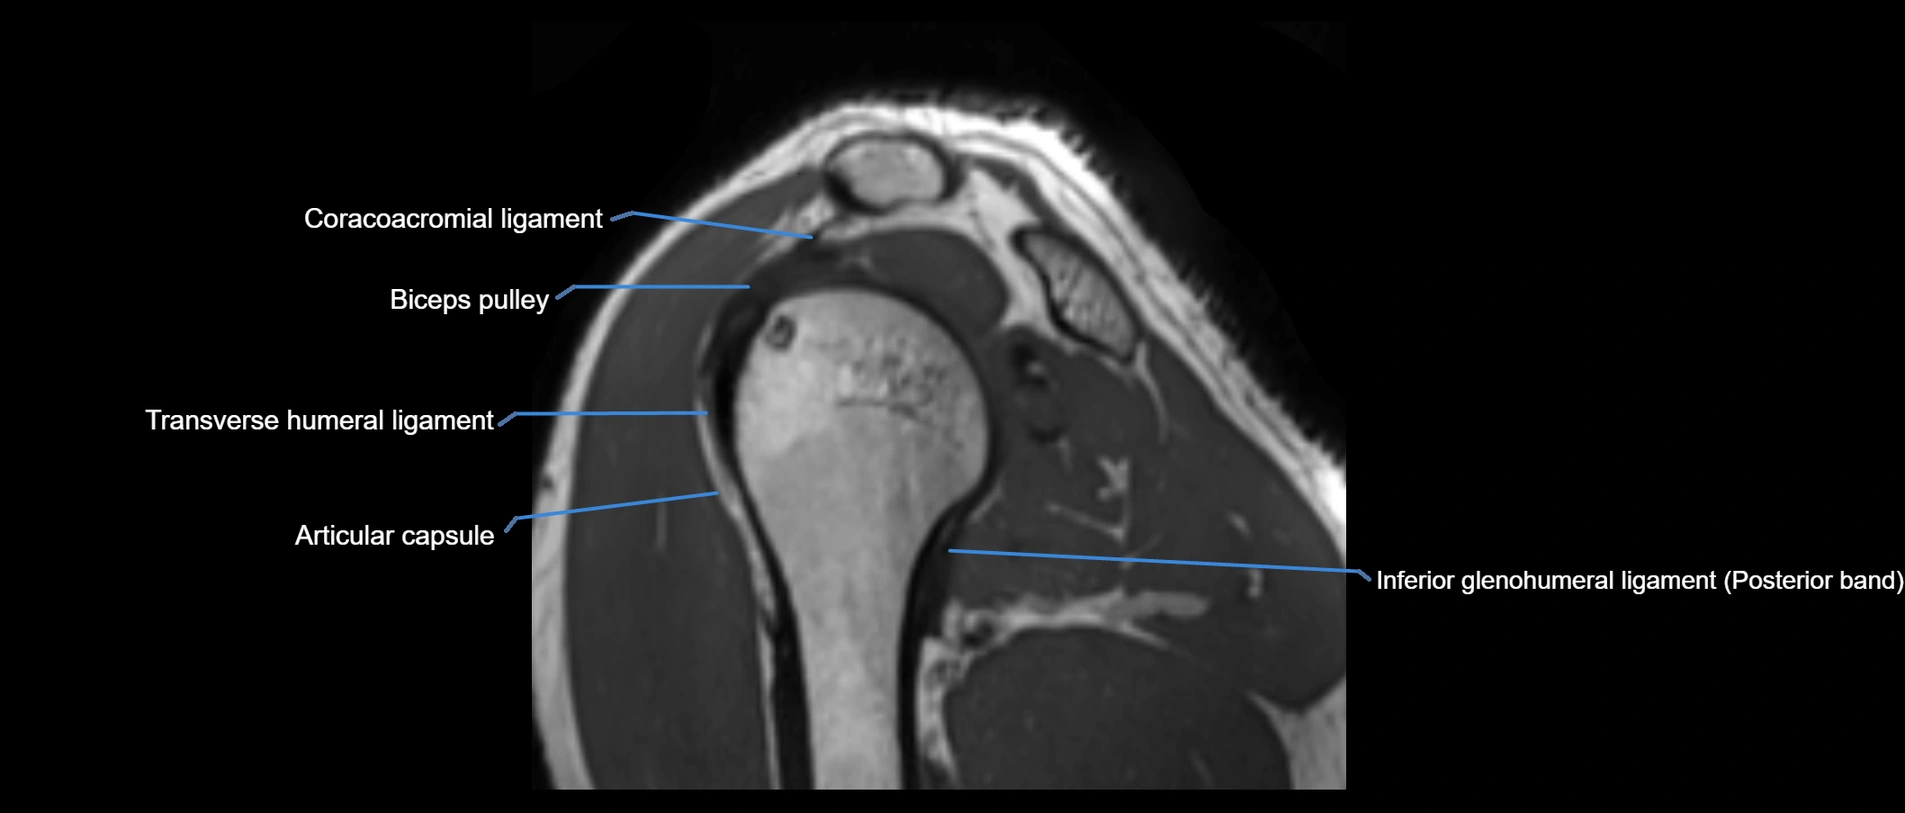

MRI images

image